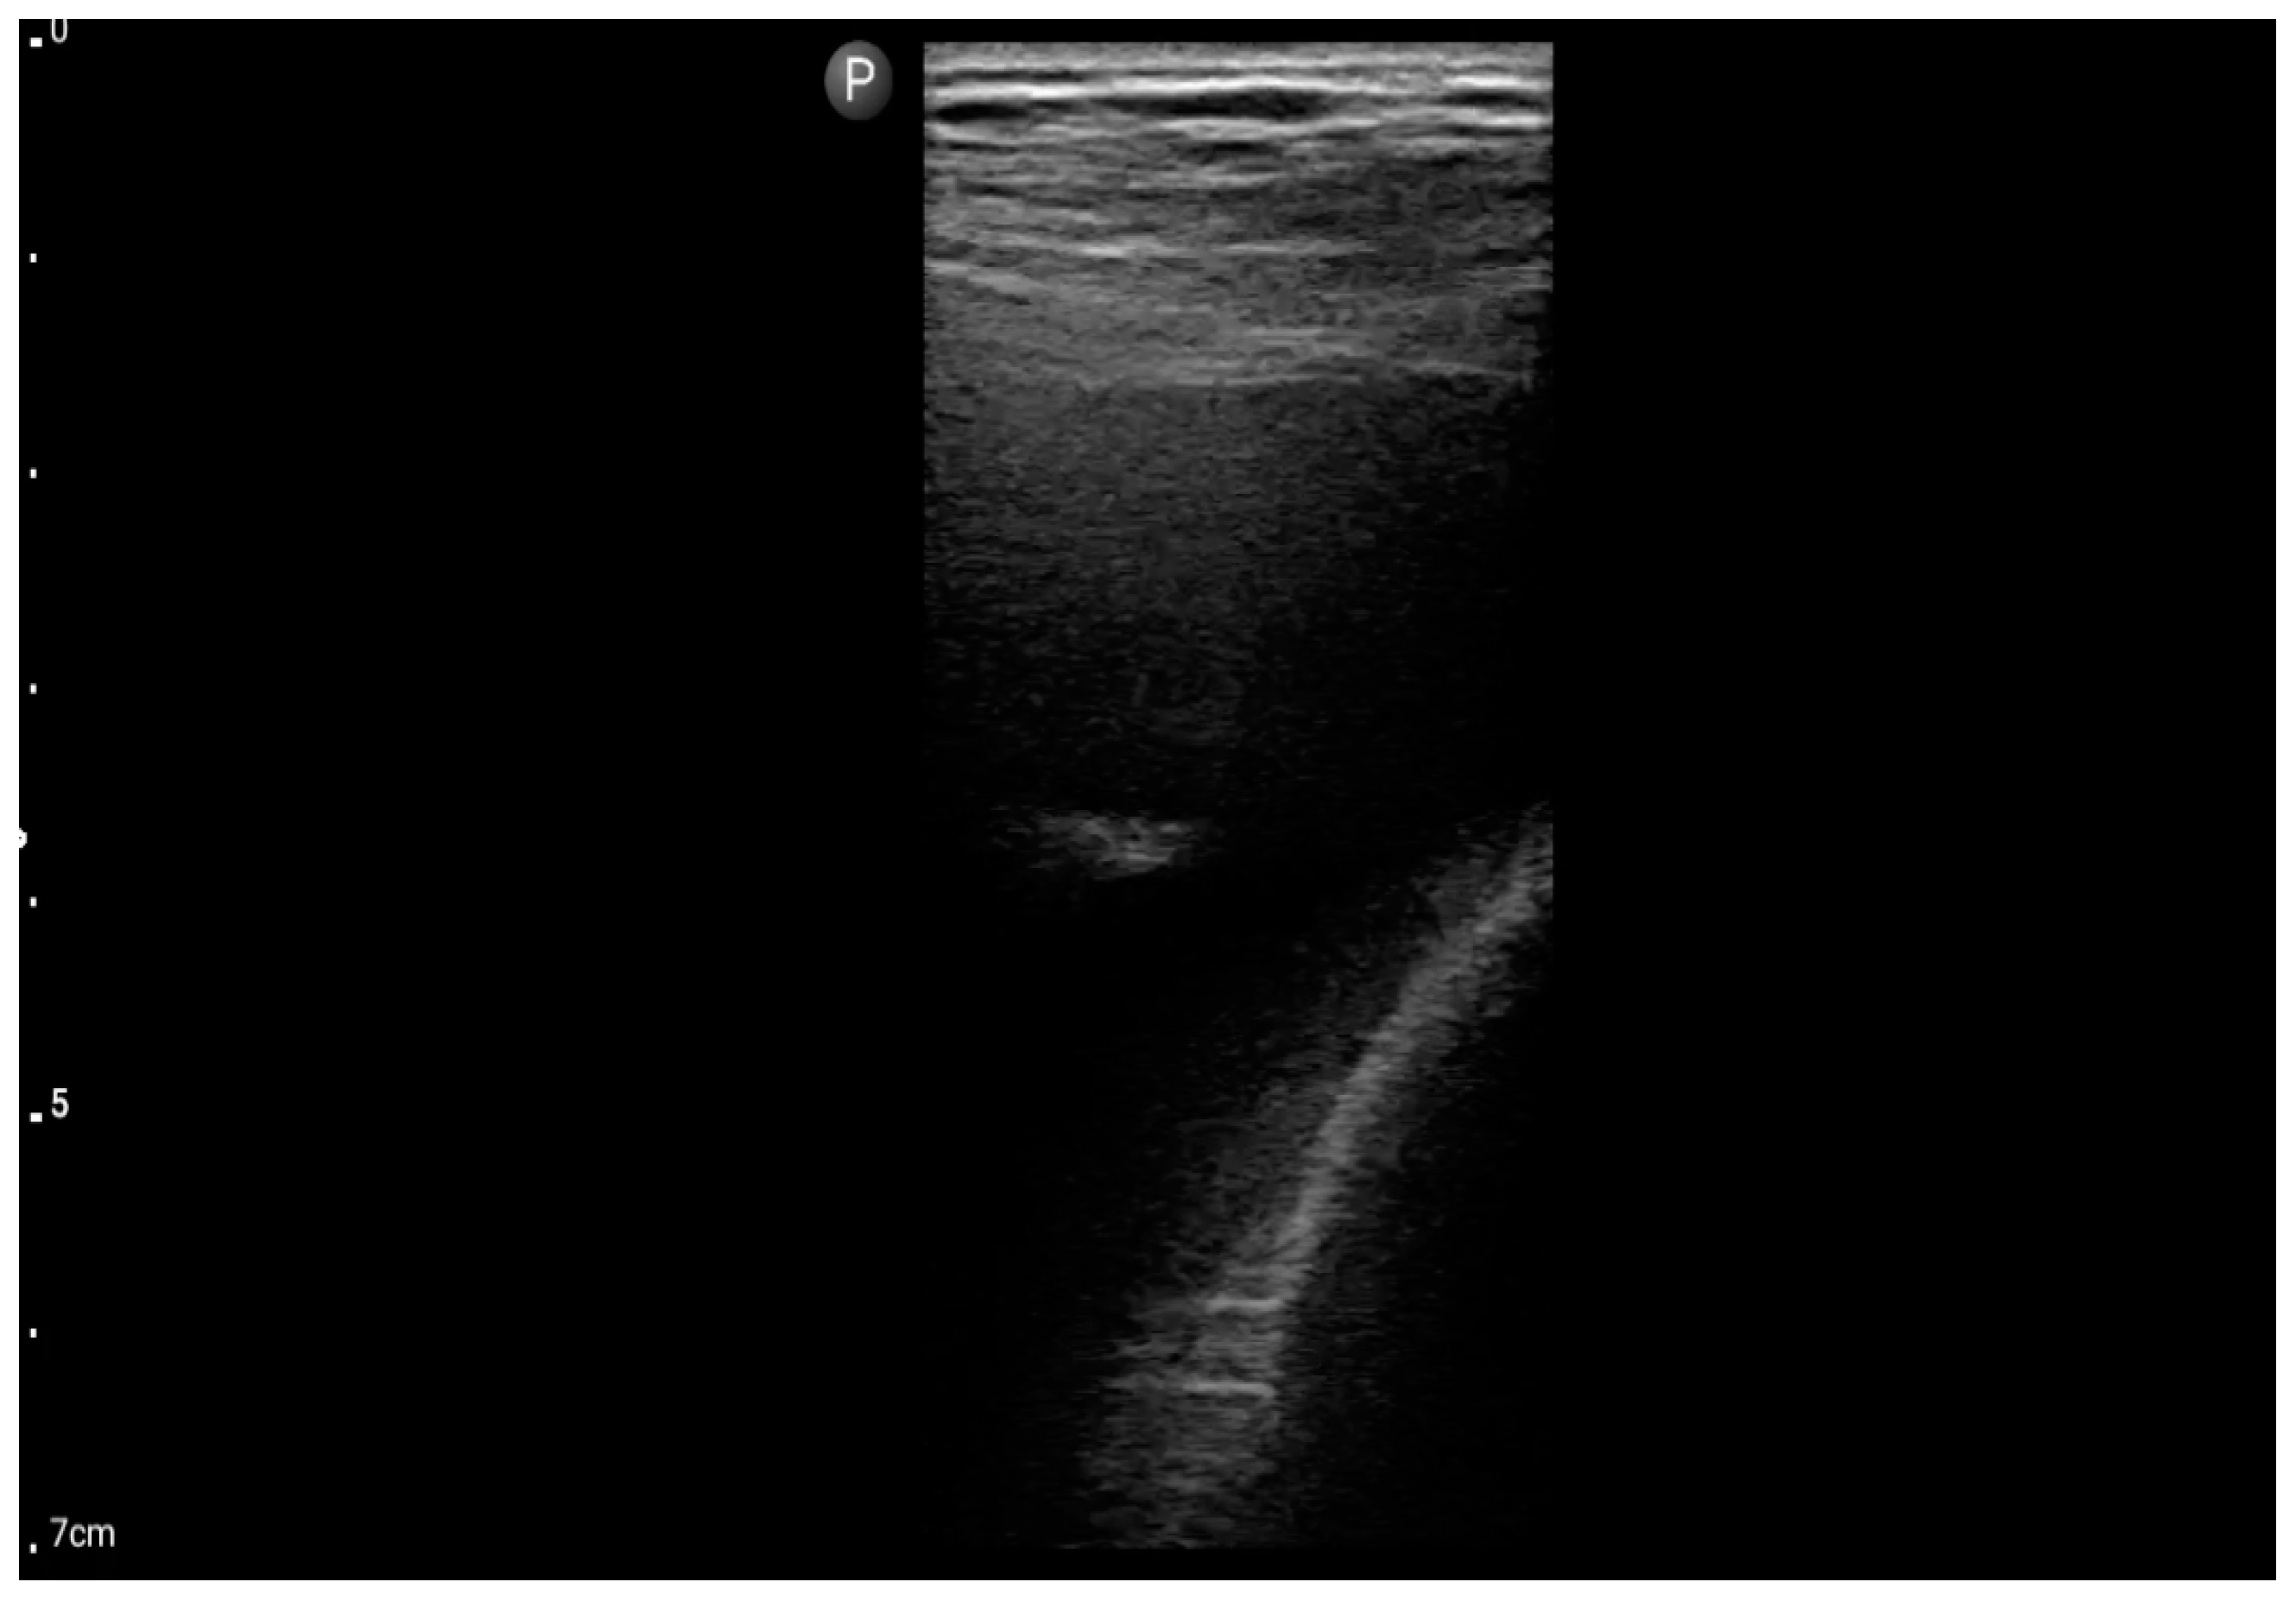

Figure 6.

Linear probe; view: Costodiaphragmatic recess—pleural effusion (BLUE protocol) (source: author’s material—DK).